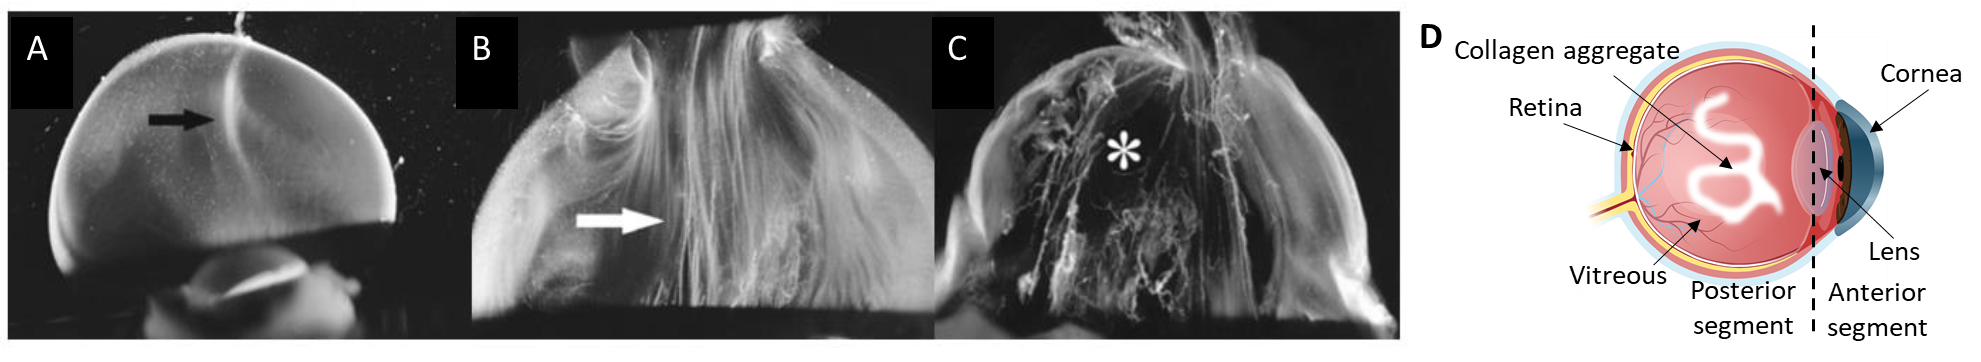

Figure 1. Dark-field slit microscopy of dissected human vitreous body reveals aging structure. (A) Homogeneous vitreous of a 33-week old fetus. (B) Fusion of collagen fibrils in the central part of the vitreous (white arrow) of an 59-year-old human. (C) Extensive fibrous liquefaction in the degenerated vitreous of an 88-year-old woman. This degeneration is accelerated in myopia and simultaneously forms vitreous opacities (D)1.

The vitreous of the eye is a transparent gel mainly composed of water, glycosaminoglycans and a network of collagen fibrils. In healthy eyes, collagen fibrils are spaced apart by hyaluronic acid (HA), an anionic glycosaminoglycan which attracts water and generates a swelling pressure that inflates the gel to maintain its transparency. Vitreous collagen fibrils are heterotypic in composition. They contain collagen type II, V, IX and XI. Type IX collagen has chondroitin sulfate glycosaminoglycan chains which extend away from the fibril surfaces; they space apart the collagen fibrils, thereby preventing the aggregation of collagen fibrils. With aging, myopia or diabetes, there is a progressive ‘liquefaction’ of the vitreous inducing the formation of collagen aggregates that scatter light and can strongly impact vision and quality of life.